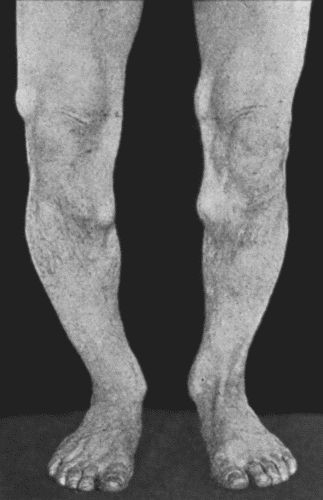

65 14.Leg Ulcers associated with Varicose Veins

71 15.Perforating Ulcers of Sole of Foot

284 66.Varicose Vein with Thrombosis

289 67.Extensive Varix of Internal Saphena System on Left Leg